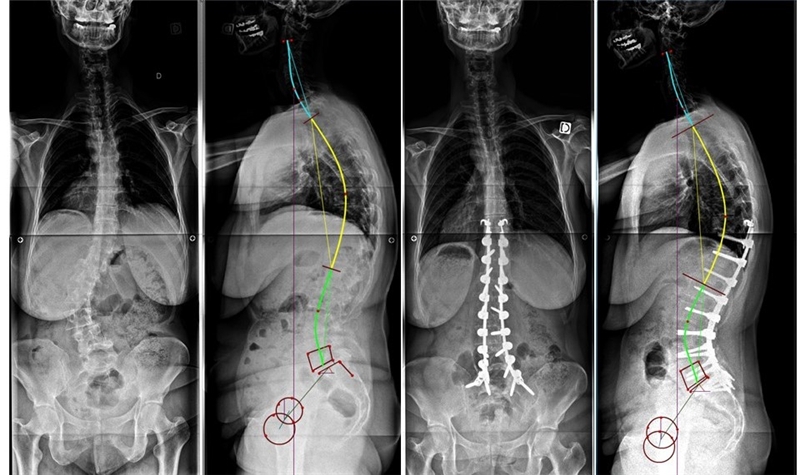

要点5:脊柱各矢状面类型的自然演变和手术决策

当PI小于50°,骨盆后倾小,PT亦较小时:

1型脊柱因腰椎前凸小而短,胸椎后凸较长,在退变历程中倾向于出现整体后凸,矢状面出现向前失平衡状态。在手术治疗中若患者无冠状面侧凸畸形,则建议维持为1型序列;若患者存在冠状面侧凸,则建议可增加一定腰椎前凸矫正至2型序列。不建议将其矫正为3型腰椎前凸,此时将发生骨盆过度前倾,导致矢状面失衡。

1型脊柱的演变与矫形策略

无侧凸畸形时维持为1型序列

存在冠状面侧凸时可增加一定腰椎前凸矫正至2型序列

2型患者的自然演变结果可能性多样,如:维持为2型,出现胸椎后凸、胸腰椎或整体后凸畸形,更严重者可发生腰椎后凸畸形。

在手术治疗2型患者时建议行短节段固定将腰椎矢状面序列维持为2型。若2型患者合并胸椎后凸畸形,建议在L4行PSO截骨矫正至1型序列;若仍维持为2型则有胸椎后凸减小的可能;若矫正至腰椎前凸较大的3型,术后发生PJK的风险较高。

2型脊柱的演变与矫形策略

2型患者将腰椎矢状面序列维持为2型

2型患者合并胸椎后凸畸形,建议在L4行PSO截骨矫正至1型序列

在整体后凸畸形的病例中,建议在L4行PSO截骨将矢状面序列矫正至1型或2型,此时应注意避免矫正至3型,因骨盆将发生前倾,继而导致矢状面向前失平衡

整体后凸畸形时在L4行PSO截骨将矢状面序列矫正至1型

当PI大于50°,骨盆后倾明显,PT较大时:

3型和4型脊柱的自然演变可能性如下:维持为3,4型,骨盆后倾转归为2型伴胸椎后凸,整体平背畸形或整体后凸畸形。在手术矫形时,仅需维持或稍增加腰椎前凸,保持为3型或4型,往往无需截骨即可达到目标。4型腰椎因其腰椎前凸较大,往往容易出现小关节骨性关节炎和退变性腰椎滑脱。

3、4型脊柱的演变与矫形策略

维持或稍增加腰椎前凸,保持为3型或4型

在骨盆后倾的2型患者合并平背畸形中,建议手术增加腰椎前凸将序列,将其矫形至3或4型,但是无法预测术后胸椎后凸的代偿和近端交界区后凸(PJK)的风险。

PI较大的2型患者合并平背畸形,将其矫形至3或4型

术后发生PJK

若骨盆后倾的2型患者合并整体后凸畸形时,建议在L3或L4行较大的PSO截骨,并行长节段融合,将脊柱矫正至3型或4型。

PI较大的2型患者合并整体后凸畸形,将脊柱矫正至3型或4型